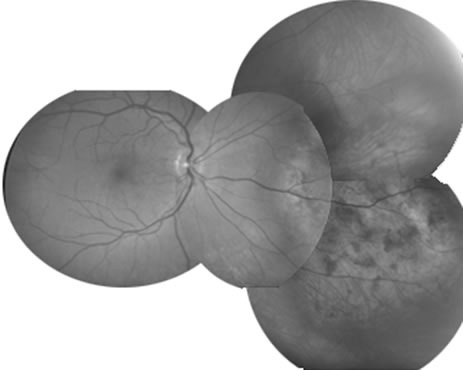

Some retinal dystrophies and degenerative processes can simulate a retinochoroiditis. Vitreous cells may occur in cases of retinitis pigmentosa. Pigmented paravenous retinochoroidal atrophy has a distinctive pattern of pigmentary deposits surrounding retinal veins; it may occur as an idiopathic degenerative disorder or sometimes as a sequela of ocular sarcoid. Fundus flavimaculatus is a rare autosomal recessive dystrophy that is usually detected in the third decade of life. It produces typical comma-shaped, yellowish retinal pigment epithelial opacities in the posterior pole, but it does not involve the macula. It can simulate a diffuse choroiditis (Fig. 24). Myopic degeneration can produce small, white, posterior pole spots that can simulate a posterior choroiditis. Peripheral fundus “paving stone” degeneration is rarely confused with an inflammatory process. These lesions show no evidence of retinal or vitreal inflammation and are quite common.54

Fig. 24. Fundus flavimaculatus. Note comma- or fish-shaped yellowish Figures at the level of pigment epithelium.